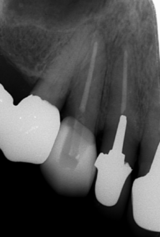

徐々に歯槽骨ももろくなり、歯周病や歯を失うリスクも高まります。

プロテタイトは、骨そのものです。(視覚的にも海綿骨とそっくりです)

骨に良い栄養を取り(骨ケア)、姿勢を正してよく嚙むことことは、下顎骨に刺激が加わり丈夫に(マウスケア)、さらに、